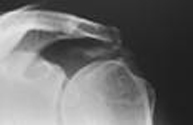

Radiografía en que se observa una calcificación

(mancha blanquecina) entre el húmero y el acromion